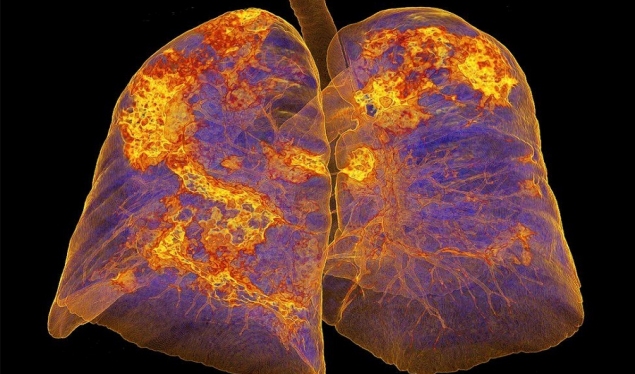

Megjithëse simptoma të tilla si dhimbje trupi, lodhje, rraskapitje dhe kollë mund të vazhdojnë për një kohë të gjatë, pacientët mund të presin përkeqësim të simptomave të frymëmarrjes – gulçim, dhimbje gjoksi, siklet, peshë. Simptoma të tilla si konfuzion dhe jerm mund të jenë gjithashtu të pranishme.

Nëse temperatura nuk ulet në ditën e 9-të ose të 10-të të infeksionit, kjo mund të tregojë pneumoni ose një infeksion të gjakut. Nëse jeni në izolim në shtëpi, kontaktoni mjekun tuaj i cili do t’ju shpjegojë se kur është koha për të shkuar në spital dhe çfarë duhet t’i kushtoni vëmendje, shkruan E-Times.